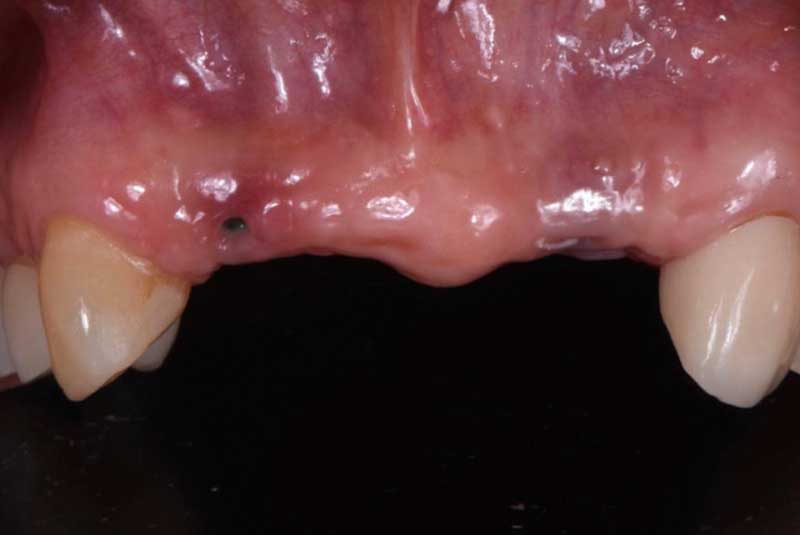

All on 6: Facial cut back (PFZ) Zirconia Full arch prosthesis for Maxilla and Mandible Before & After